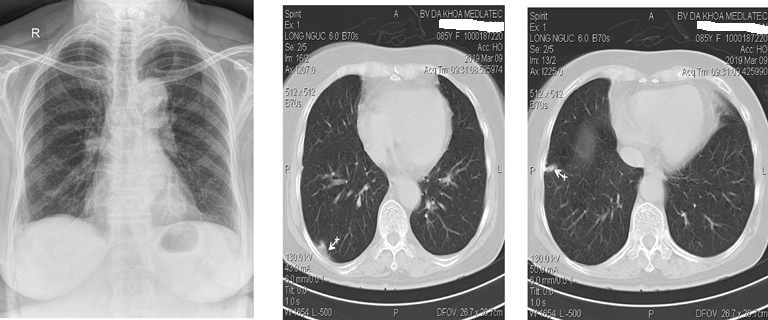

Lực lượng Đặc nhiệm Dịch vụ Dự phòng Hoa Kỳ khuyến nghị sàng lọc phổi hàng năm bằng CT ngực liều thấp (LDCT) cho những người từ 50 đến 80 tuổi có nguy cơ mắc ung thư phổi cao, chẳng hạn như những người hút thuốc lâu năm. Cùng với hình ảnh của phổi, các bản quét cũng cung cấp thông tin về các cấu trúc khác trong ngực.

Khi chúng tôi xem xét các hình ảnh CT, trọng tâm chính là xác định các nốt nghi ngờ ung thư phổi, nhưng có nhiều thông tin giải phẫu hơn được mã hóa trong không gian, bao gồm cả thông tin về thành phần cơ thể."

Xu và các đồng nghiệp trước đây đã phát triển, thử nghiệm và phát hành công khai một thuật toán AI tự động lấy các phép đo thành phần cơ thể từ LDCT sàng lọc phổi. Thành phần cơ thể là thước đo tỷ lệ mỡ, cơ và xương trong cơ thể. Thành phần cơ thể bất thường, chẳng hạn như béo phì và mất khối lượng cơ, có liên quan đến các tình trạng sức khỏe mãn tính như rối loạn chuyển hóa. Các nghiên cứu cũng chỉ ra rằng thành phần cơ thể rất hữu ích trong việc phân tầng nguy cơ và tiên lượng bệnh tim mạch và bệnh phổi tắc nghẽn mạn tính. Trong điều trị ung thư phổi, thành phần cơ thể đã được chứng minh là có ảnh hưởng đến khả năng sống sót và chất lượng cuộc sống.

Đối với nghiên cứu mới, nhà nghiên cứu đã đánh giá giá trị gia tăng của các phép đo thành phần cơ thể có nguồn gốc từ AI. Họ đã sử dụng ảnh chụp CT của hơn 20.000 cá nhân được rút ra từ Thử nghiệm sàng lọc phổi quốc gia.